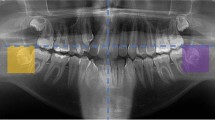

Self-constructed malocclusion dataset by collecting and organizing oral sweep data from real cases. As shown in Table 2, the distribution of various categories within the dataset is clearly presented. Among them, due to the small amount of data on implant screw residual roots, we expanded it to twice the expansion multiple of other deformities during training. Figure 6 focuses on the visualization of malformed teeth in the dataset, displaying the specific morphological characteristics of dental anomalies in an intuitive graphical format. This dataset comprises 1103 half-jaw malformed dental models, covering nine major categories of anomalies: wisdom teeth, High and low drop teeth, missing teeth, erupting small teeth, diastema, dental crowding, implant screw residual roots, crown deformities, and Da Vinci-like black triangles. Among these, wisdom teeth data are divided into four scenarios: full scans of two wisdom teeth, partial scans of two wisdom teeth, full scans of one wisdom tooth, and partial scans of one wisdom tooth. Data on missing teeth include missing wisdom teeth and single and multiple missing teeth, with the most severe cases involving only eight remaining teeth. Erupting small teeth data primarily originate from collections during the tooth replacement period in children. Dental crowding data encompass various conditions such as narrow dental arches, excessive interdental spacing, and malpositioned teeth. Da Vinci-like black triangle data reflect triangular gaps caused by gingival recession or loss of periodontal tissue.

Compared to 3DTeethSeg2228, the proposed dataset contains a significant number of malformed teeth. Additionally, 3DTeethSeg22 is obtained through indirect scanning and includes plaster bases. In contrast, the proposed dataset utilizes intraoral scanning technology, which effectively reduces errors introduced during the mold-making process. This technology also enables the acquisition of more precise oral structure data, making it closer to real-world oral environments. Furthermore, when processing these malformed dental models, the segmentation task faces considerable challenges due to the common manifestations of dental anomalies, such as tooth crowding, misalignment, or large-scale displacement.